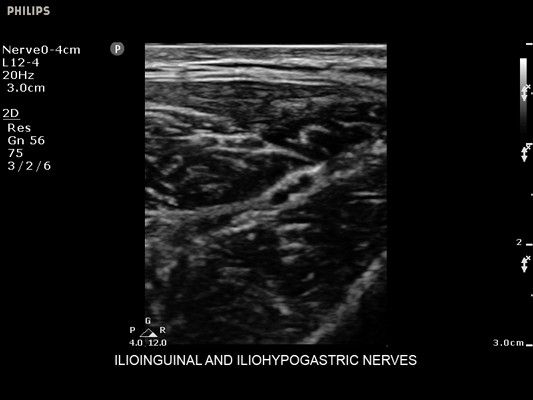

• Метки центральной линии на датчиках L12-4 и C6-2 для упрощения внеплоскостной навигации

• Диагностика нервов

• Линейный УЗИ датчик Philips L12-4